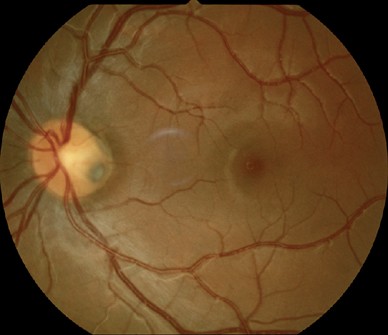

APON은 단순한 망막섬유층의 패임(notching)정도보다 더 깊게 패이는 것으로,

사상판에 도달할 정도와, 시신경유두의 가장자리에 닿을 정도로 국소적인 망막신경섬유층의 상실이 있음을 의미합니다.

즉, 사상판 위쪽에 존재해야하는 망막신경섬유층이 완전히 상실되면서,

사상판이 완전히 노출되는 것으로, 하얀게 사상판 조직을 직접 관찰할수 있습니다.

1/3에서는 시신경유두의 상극단의 귀쪽에서,

2/3에서는 시신경유두의 하극단의 귀쪽에서, 발견되는데,